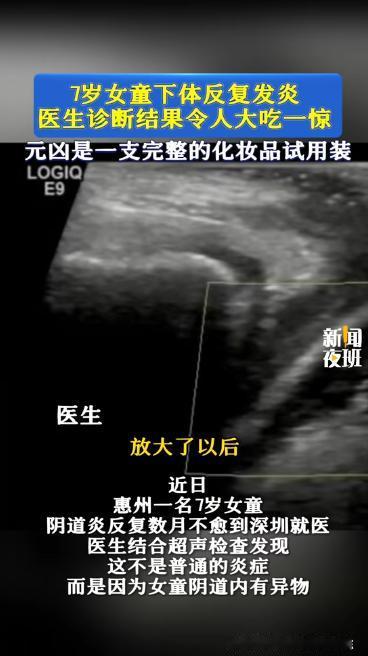

事情是这样的,一个来自惠州的小女孩,阴道炎反反复复好几个月,一直治不好,家里人也以为是普通感染,拖了一段时间,后来实在不见好,才带她去深圳市妇幼保健院做更详细的检查。

医生随即安排进一步检查,结果证实了判断,阴道内确实有东西,而且已经存在一段时间了,接下来就是怎么安全把它取出来的问题。

这次操作是由张主任(化名)医师带队,用的是阴道内镜的微创方式,简单理解,就是用一个很细的内镜进去看清楚,再把东西取出来,尽量不伤到组织。

当内镜深入探察,在场医护皆感意外,原来,内部卡住的异物竟是一整支精华液小样,虽其体积小巧,却严丝合缝地卡在其中,估摸已滞留近一月之久。